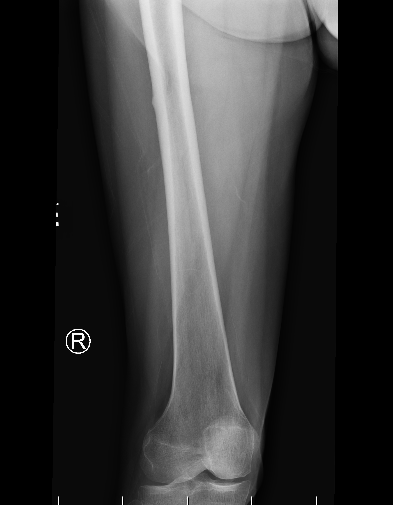

Stress Fracture Lateral

Incomplete femoral shaft AFF / dreaded black line

Xray

Periosteal stress reactions / beaking

Thickening of the lateral cortex

- tension side

- most common in the subtrochanteric region

- can be in shaft

Lateral beaking femoral shaft